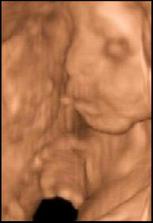

- 11.1.10 sme boli na 3D a pan doktor nam povedal ze to vyzera na DIEVČATKO 🙂